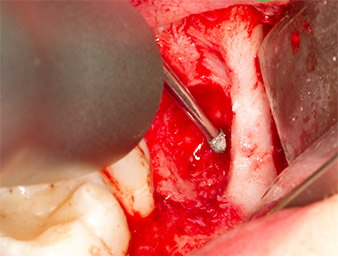

To expose the root remnant with as little trauma as possible to the tissue, a further instrument was used (Piezomed S2) that is primarily indicated for preparing the lateral window in augmentations of the sinus floor. The diamond-coated ball was additionally used to smooth sharp bone edges (Fig. 6 and 7). All the Piezomed attachments were used with the relevant automatic default setting without booster function.